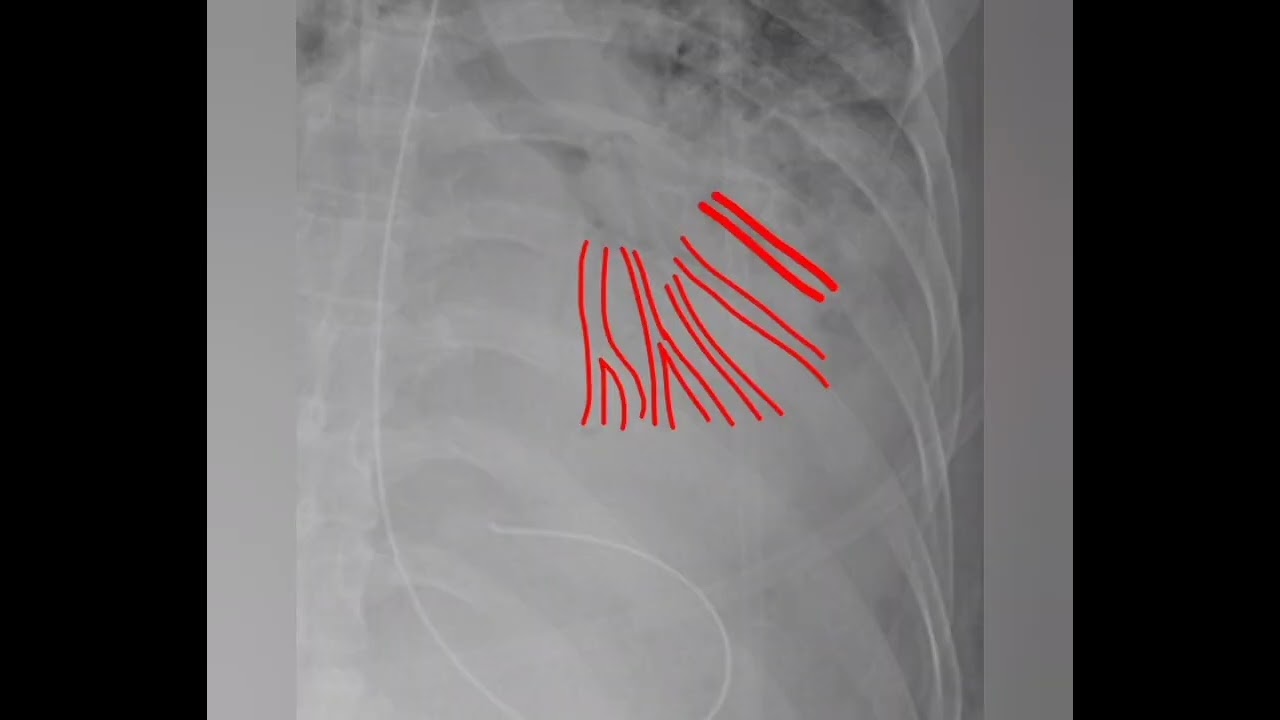

Air bronchogram sign indicates alveolar pathology with patent bronchi.

Commonly seen in consolidation.